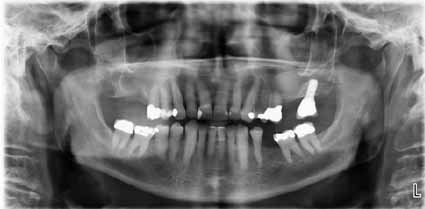

歯科医師は、急性または慢性の副鼻腔炎について、歯科的な原因があるかどうかを調べるよう依頼されることがよくあります。明らかな歯の感染症や原因歯のある側(片側)の上顎洞炎の場合、一般歯科医師は、臨床検査、X線撮影、口腔内画像、OPGに基づいて、歯性副鼻腔炎を診断することができます。しかし、口腔内画像診断しか利用できない場合、診断は複雑になり、経験豊富な臨床医でも発見が困難になることがあります。発見が比較的難しい疾患としては、副鼻腔に拡がる嚢胞や良性腫瘍、あるいは歯を介して発生する二次感染などがあります。上顎第三大臼歯の埋伏が疑われる場合は、徹底的なX線検査が不可欠です。根分岐部における歯周ポケットの形成は、副鼻腔にまで広がり、長期にわたる副鼻腔炎を引き起こす可能性があります。そのため、一般歯科医が誤って患者の歯を抜歯してしまうことも珍しくありません。治療担当医師が疑わしい状態と判断した場合は、口腔顎顔面外科のクリニックへの紹介、または CBCTによるさらなる検査が推奨されます。

- 口腔内X線撮影、続いて高品質の根尖X線撮影およびOPG撮影。診断が困難な場合や病変が疑われる場合は、必要に応じてCBCTも実施。

文献によると、上顎洞炎の10~12%は歯が原因であると言われていますが、症例の最大50%は歯原性である可能性があると推測されています。したがって、慢性の片側性慢性副鼻腔炎の場合は、慎重な歯科検査が必要です。ただし、決定的な処置を行うには、明確な病状と因果関係が必要です。

- 小臼歯/大臼歯領域の歯根尖/歯周領域における放射線透過性(画像3a、画像3b)

- 歯根尖/歯周領域における放射線透過性を示すCTスキャン(画像3c)